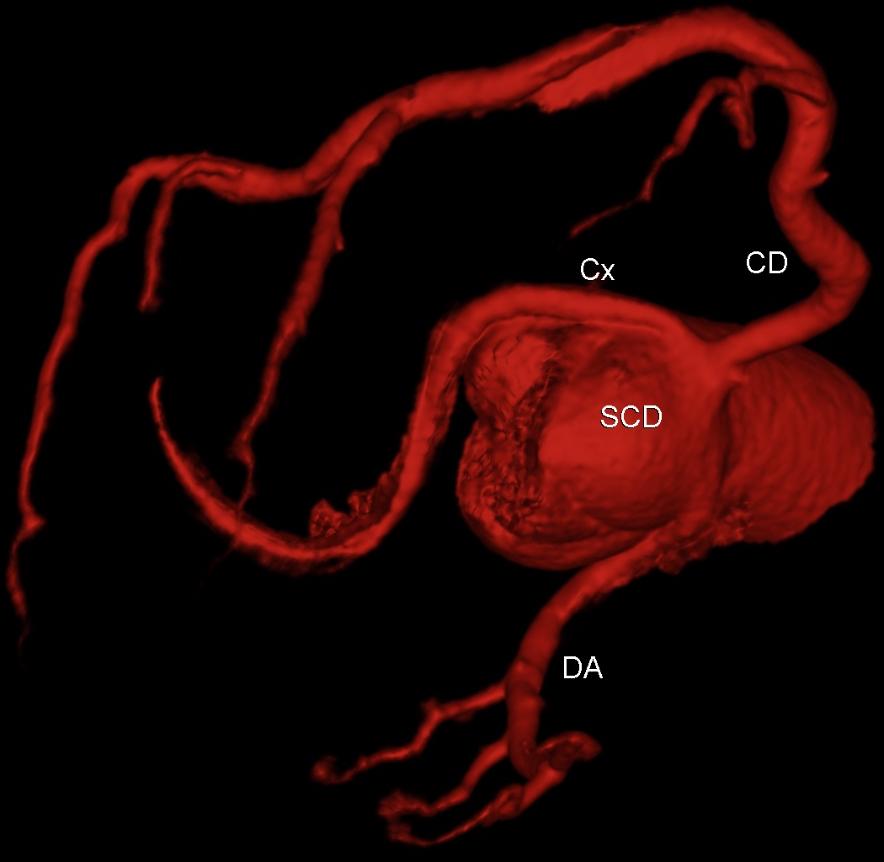

Enquanto a Copa do Mundo 2022 começava no Catar, era publicada no JACC uma revisão campeã sobre o estado da arte na abordagem da doença de tronco da coronária esquerda significativa, isto é, com esten…